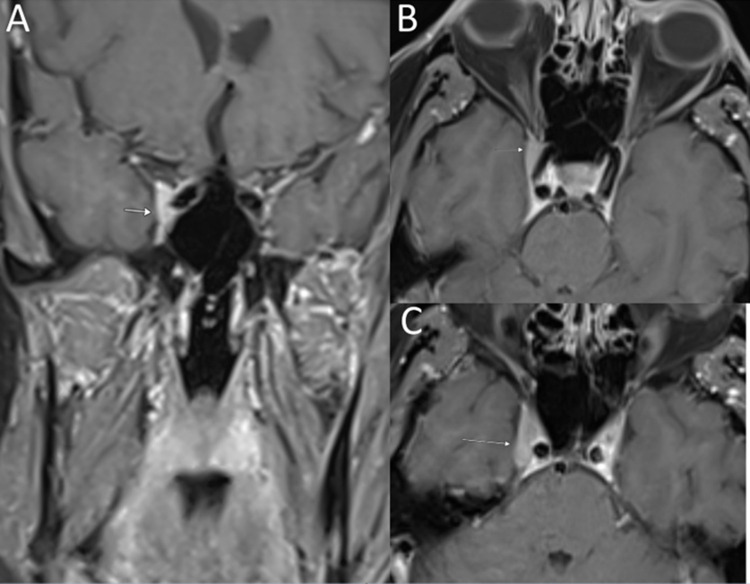

原发性颅神经淋巴瘤病(PCNL)是原发性中枢神经系统淋巴瘤(PCNSL)的一种罕见亚型,淋巴瘤浸润累及范围仅限于颅神经。在此,我们报告了一例成功进行基因组分析的 PCNL 病例。一名 57 岁的男性患者在诊断前经历了长达约 30 个月的漫长阶段,主要表现为通过类固醇治疗的多次颅神经痛。确诊时,患者右侧颅神经病变,累及颅神经(CN)V、VI 和 VII。右侧海绵状病变活检的病理结果与大 B 细胞淋巴瘤浸润神经纤维一致。患者的临床病程具有侵袭性和难治性,特点是病情无情发展,出现颈椎神经淋巴瘤病、脑脊液受累、脑外膜和脑实质内受累,尽管采用了多种疗法,包括化疗免疫疗法、布鲁顿酪氨酸激酶抑制剂、放射治疗、自体干细胞移植、嵌合抗原受体T细胞疗法(CAR-T)和全脑放射治疗。患者从最初诊断时起存活了22个月,在首次颅神经病变发作后存活了52个月。新一代测序发现了 PCNSL 中经常出现的突变(MYD88、CD79b 和 PIM1)。不寻常的发现包括涉及 PIM1 的总共 22 个突变,表明存在高度活跃的异常体细胞高突变和两个错义 CXCR4 突变。CXCR4突变从未在PCNSL中出现过,可能会对疾病生物学和治疗干预产生影响。我们通过文献综述来进一步阐明 PCNL。

Primary cranial neurolymphomatosis (PCNL) is a rare subtype of primary CNS lymphoma (PCNSL) in which infiltrative lymphomatous involvement is confined to cranial nerves. Here, we report a case of PCNL with successful genomic profiling. A 57-year-old male had a lengthy prediagnostic phase spanning approximately 30 months, characterized by multiple episodes of cranial neuropathies managed by steroids. At the time of diagnosis, the patient had right-sided cranial neuropathies involving cranial nerves (CN) V, VI, and VII. Pathological findings of the right cavernous lesion biopsy were consistent with large B-cell lymphoma-infiltrating nerve fibers. The clinical course was aggressive and refractory, characterized by relentless progression with the development of cervical spinal neurolymphomatosis, cerebrospinal fluid involvement, and ependymal and intraparenchymal cerebral involvement, despite multiple lines of therapy, including chemoimmunotherapy, Bruton's tyrosine kinase inhibitor, radiation, autologous stem cell transplant, chimeric antigen receptor T-cell therapy (CAR-T), and whole-brain radiation. The patient survived for 22 months from the time of the initial diagnosis and 52 months after the first episode of cranial neuropathy. Next-generation sequencing identified mutations (MYD88, CD79b, and PIM1) that are frequently observed in PCNSL. The unusual findings included a total of 22 mutations involving PIM1, indicating a highly active aberrant somatic hypermutation and two missense CXCR4 mutations. CXCR4 mutations have never been described in PCNSL and may have implications for disease biology and therapeutic interventions. We provide a literature review to further elucidate PCNL.